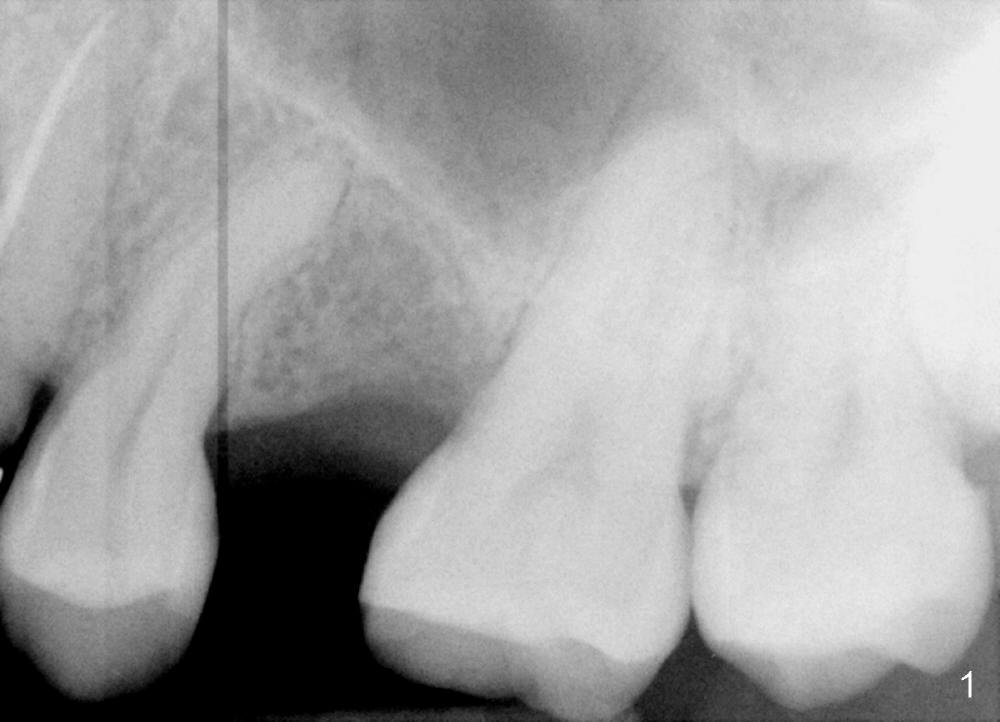

PA in Fig.1 is taken 8 months after exfoliation of the previous implant. It appears that the bone heals. One-piece implant (3x11 mm) is to be placed following tissue punch (Fig.2 green). If insertion torque is high, an immediate provisional will be fabricated (Fig.3 red). Once the implant osteointegrates, a rubber separator will be used repeatedly to move the 1st premolar mesially (arrow).

The 2nd option is to place 3.5 or 4x11 mm 2 piece implant. Try not to perforate the sinus floor initially, which causes infection, leading to implant failure. After 3 or 3.5 mm tissue punch (from DIO 1 piece implant kit), use 1.6 mm pilot drill, followed by 2.6 mm bone expander at the depth of 9 mm. Take PA after each step to confirm the depth. Use the implant to lift the sinus floor. If the latter fails, use 2.5 mm Bicon osteotome to do sinus lift with Osteogen, followed by implant placement. What is the intraop decision?